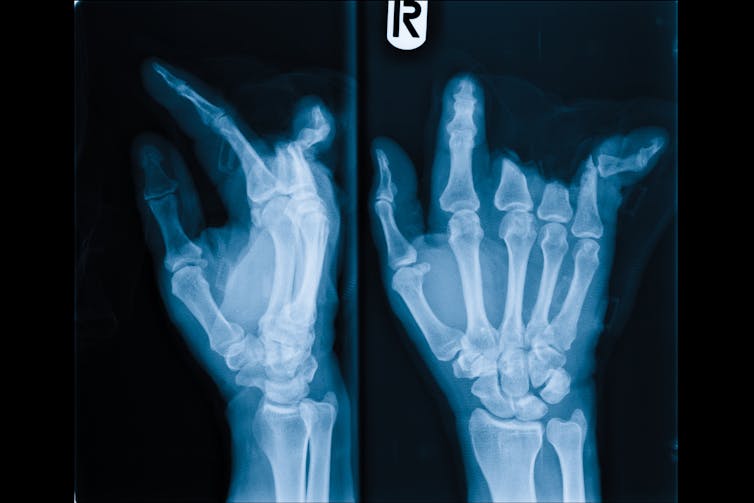

To dig deeper, we experimentally caused temporary sensory deprivation in a group of volunteers and compared the results with those of a control group – a total of 36 participants. Using a simple anesthetic – Lidocaine, like you get at the dentist – we blocked touch and movement perception of a single finger of our participants. The anesthetic was applied twice (on consecutive days), and lasted about two hours.

We found that this very small period of deprivation lead to significant improvements in touch perception of the finger directly adjacent to the anesthetized finger, with no changes in the other digits. Why just the neighboring finger? Research with primates shows that when one finger is lost, it’s mostly the neighboring fingers that claim the missing finger brain territory.

Our results show that the brain immediately boosted touch perception in one of the remaining fingers of our “temporary finger amputees” – suggesting short term deprivation can indeed have functional benefits for perception, without training.